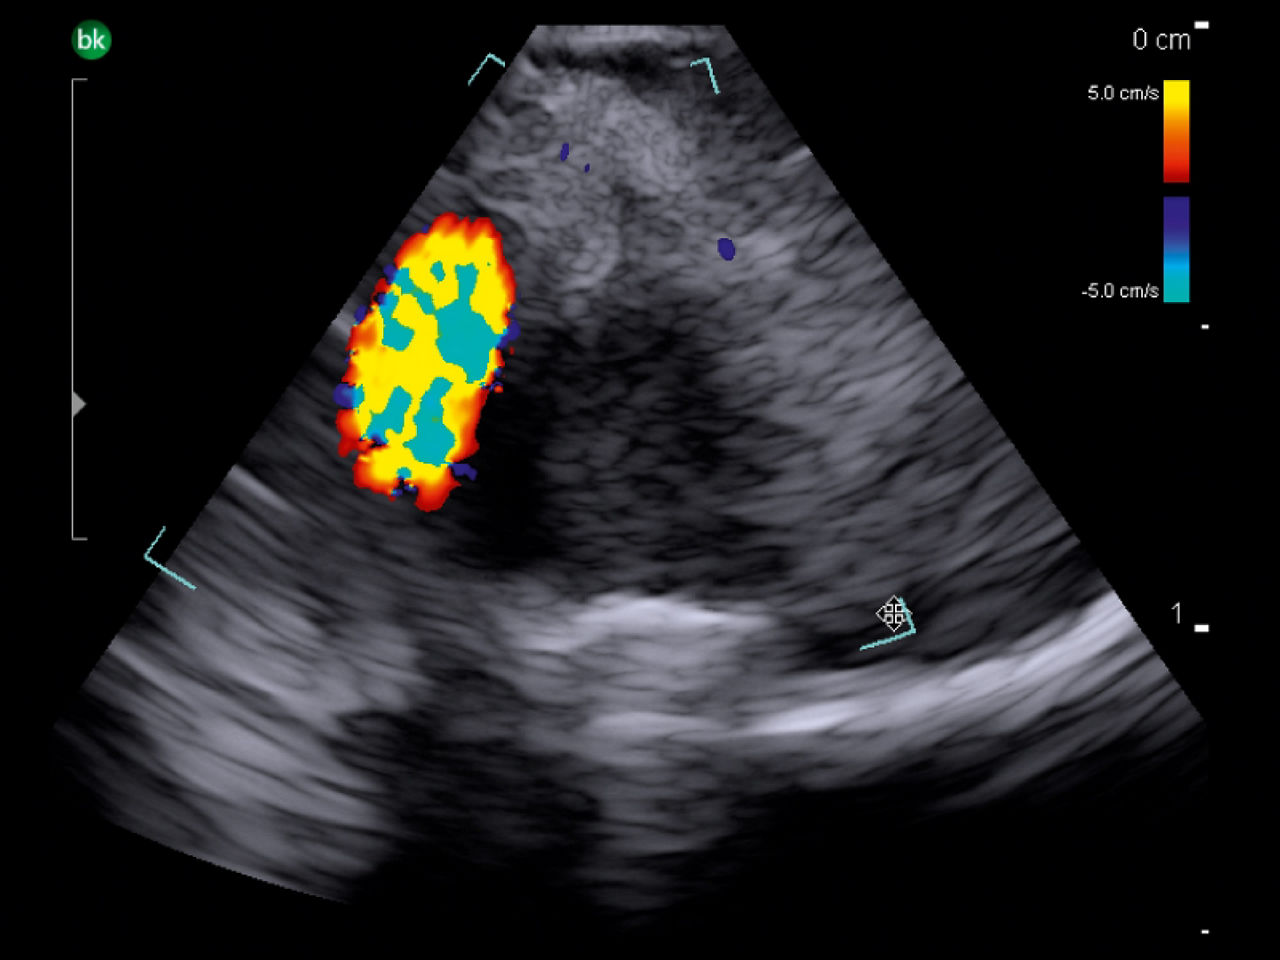

Neurovascular

Shorten operative time with intraoperative ultrasound³. Use intraoperative ultrasound during surgery to: locate AVM nidus and identify feeding arteries with color Doppler, assess for resection of AVMs⁴, identify associated hematoma⁵, and visualize preoperative embolization (e.g. Onyx®).